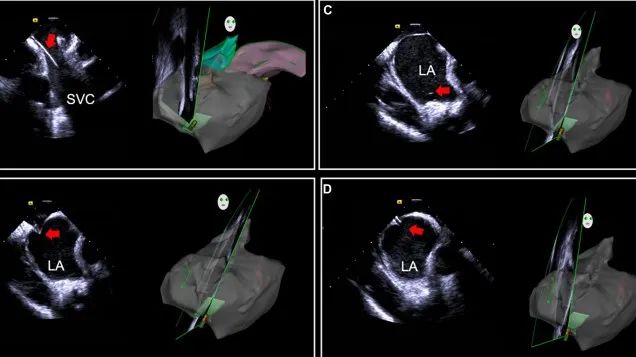

一種與心導(dǎo)管檢查相結(jié)合的超聲心動(dòng)圖診斷新興技術(shù),通過將超聲探頭置于心腔內(nèi)部,發(fā)射并接收超聲信號(hào),來精確獲取心臟解剖結(jié)構(gòu)、心臟血流動(dòng)力學(xué)等信息的實(shí)時(shí)成像。與其他影像技術(shù)相比,ICE技術(shù)具有操作簡單、無輻射、安全性高、手術(shù)效率高、實(shí)用等優(yōu)勢(shì),ICE在很大程度上有望取代經(jīng)食道超聲心動(dòng)圖(TEE),成為電生理和結(jié)構(gòu)性心臟病領(lǐng)域的理想成像方式。

目前ICE技術(shù)已被應(yīng)用于左心耳封堵、房顫射頻消融、二尖瓣成形、房間隔缺損封堵等多種心臟介入手術(shù),應(yīng)用場(chǎng)景主要圍繞心臟電生理、結(jié)構(gòu)性心臟病等領(lǐng)域,目前以電生理應(yīng)用為主。數(shù)據(jù)顯示,我國結(jié)構(gòu)性心臟病介入器械市場(chǎng)規(guī)模已從2017年的4億元增長至2021年的20億元,年復(fù)合增長率達(dá)48.3%;預(yù)計(jì)到2025年,該市場(chǎng)規(guī)模將達(dá)到104億元,可以預(yù)見ICE市場(chǎng)規(guī)模也將同步高速增長,未來市場(chǎng)發(fā)展空間廣闊。

心腔內(nèi)超聲(ICE)技術(shù)壁壘極高,國內(nèi)主要廠商核心部件仍舊為進(jìn)口,集成了超聲和圖像處理最前端技術(shù),包括超聲探頭、線纜、軟件成像算法等,是當(dāng)前內(nèi)窺超聲方向最具挑戰(zhàn)的領(lǐng)域。ICE的應(yīng)用經(jīng)歷了2D平面成像、3D三維立體成像、以及4D的實(shí)時(shí)三維立體成像階段。